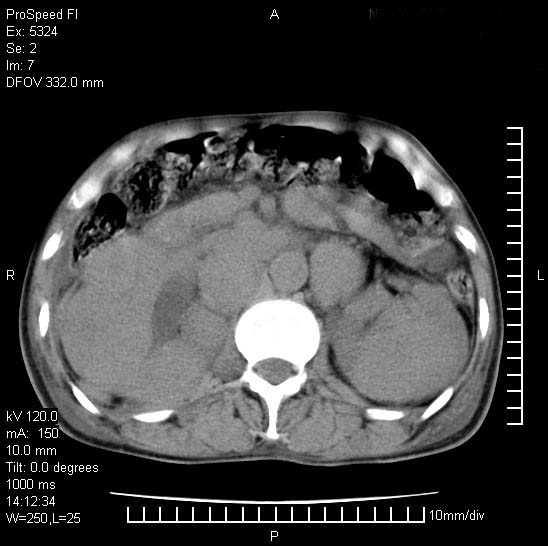

患者阴囊肿大14月,腰痛2个月,咳嗽,咳痰1周,患者现在肾功异常,做增强有些担心,我们用的是欧乃派克.

右侧肾癌伴腹膜后淋巴结转移!

右侧肾癌后腹膜转移,腹腔少量积液

腹膜后淋巴结肿大包饶腔静脉,双肾病变,建议增强

双肾均有软组织密度舯物,腹膜后淋巴结肿大包饶腔静脉------考虑为恶性占位病变,转移瘤可能。

支持:双肾均见软组织密度肿块影,腹膜后淋巴结肿大包绕腔静脉------考虑为恶性占位病变,转移瘤可能。

1)考虑双肾恶性肿瘤(肾癌?)。2)腹膜后淋巴结肿大,多为肿瘤转移所致。

腹腔积液,双肾均有稍高密度肿块,主动脉旁广泛淋巴结肿大,融合,无显著肿块坏死征像,多考虑淋巴瘤累及双肾,不排除肾癌伴转移(肾癌这么大应该较多坏死了),另阴囊肿大,不知是实质肿大还是阴囊积液,如是是积液,多为腹腔肿块压近睾丸静脉所致,如是是实性的,多为淋巴瘤

1、淋巴瘤,双肾转移瘤;2、双侧肾癌,伴有腹膜后淋巴结转移。

双肾均有软组织肿块伴腹膜后淋巴结肿大融合,右侧结肠旁沟积液;考虑恶性肿瘤。转移瘤?淋巴瘤?

双肾增大,腹膜后多发肿大淋巴结影.首先考虑淋巴瘤.

双肾增大,结合腹膜后淋巴结肿大,考虑双肾恶性肿瘤并转移可能。

双肾癌并腹膜后淋巴结转移

考虑恶性淋巴瘤侵及双肾,腹膜后淋巴结肿大。